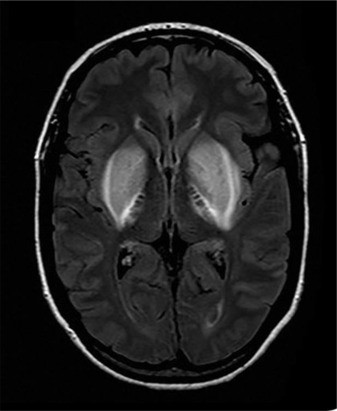

TAG: kerusakan otak